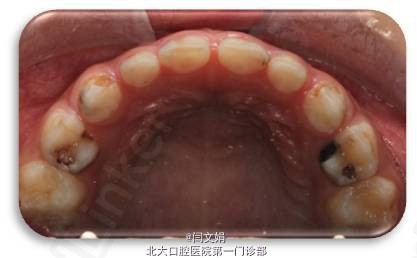

左下后牙色黑一周余,否认自发痛夜间痛史及其他不适。

全口卫生状况较差,牙面大量软垢。 75MOBP大面积龋坏,色棕黄,质软,叩痛(-),不松动,牙龈未见红肿瘘管。 X线片示:根尖未见低密度影, 35牙胚未见。 全口曲面断层片示:15,25,35,45,14,24,34,44,1,2,22,32,42恒牙胚未见,11与13间见一畸形牙胚影像。第一二恒磨牙牙胚存,第三恒磨牙未见。21牙胚扭转。

诊断:75MOBP深龋;15,25,35,45,14,24,34,44,1,2,22,32,42先天缺失 处理:75MOBP充填后预成冠修复,治疗其余龋坏牙, 待成年后修复缺失牙